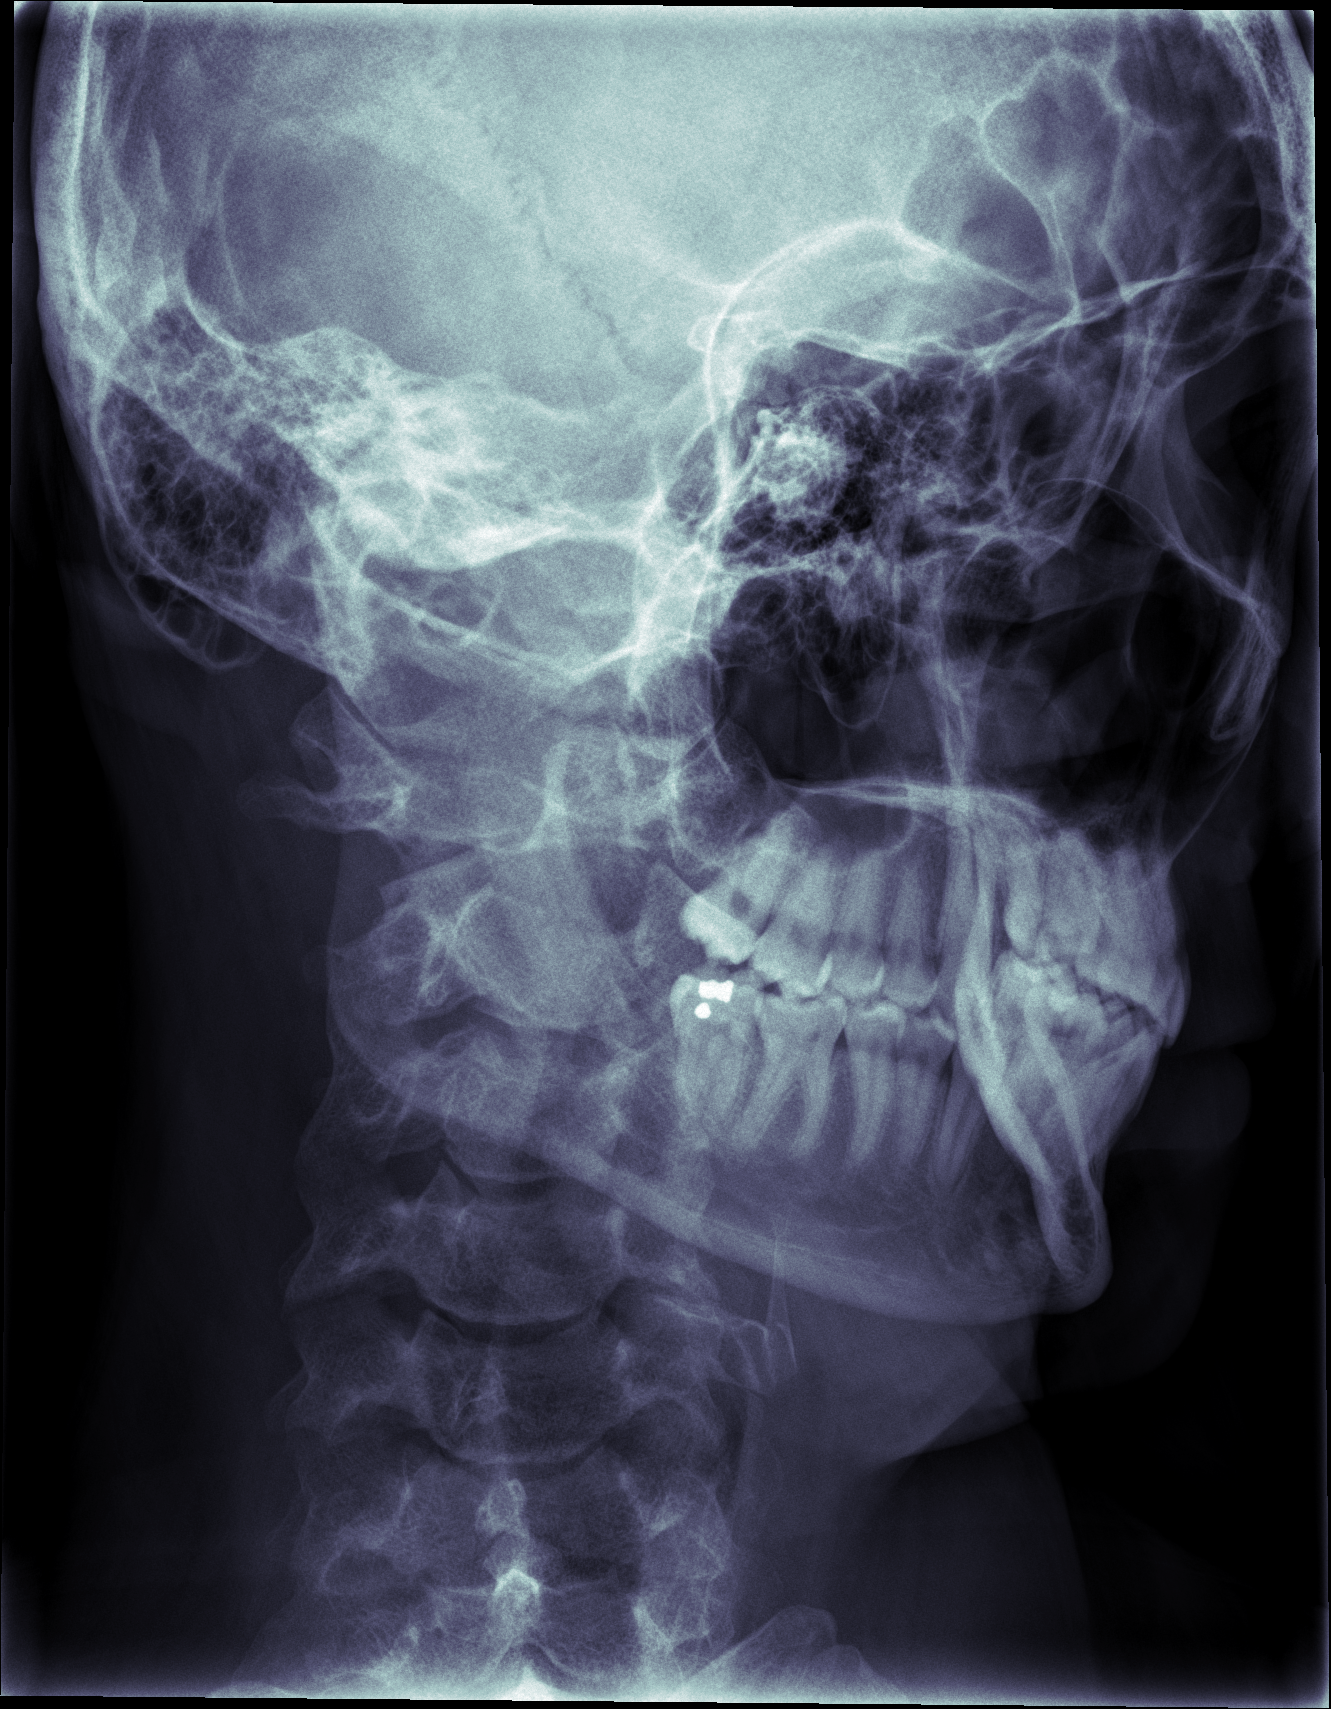

The suture across my right skull really stands out.

I wonder where the bones in my midface are. Is the sinus cavity really that big? Is my maxilla just really out of focus?